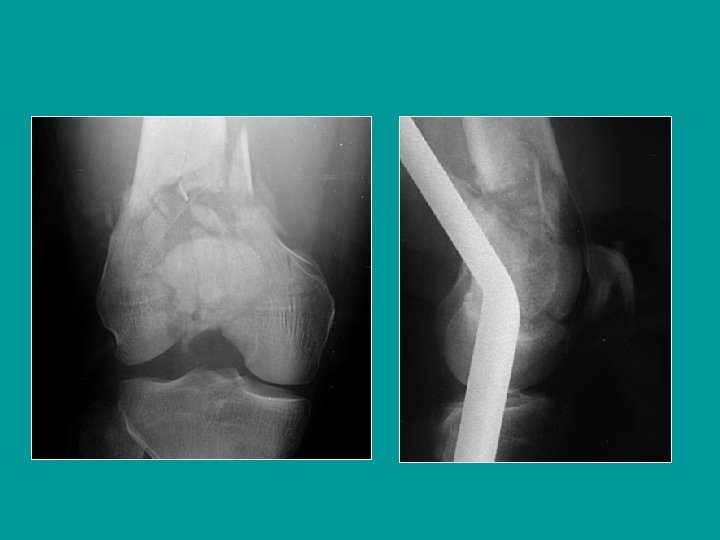

Déplacement des fractures supra condyliennes Bascule en arrière et en bas du fragment distal (jumeaux) Saillie en avant du fragment proximal qui refoule le quadriceps

Fracture sus et intercondylienne Fracture comminutive articulaire

Réduction par traction trans tibiale

La correction de la bascule requiert une traction forte et un appui postérieur